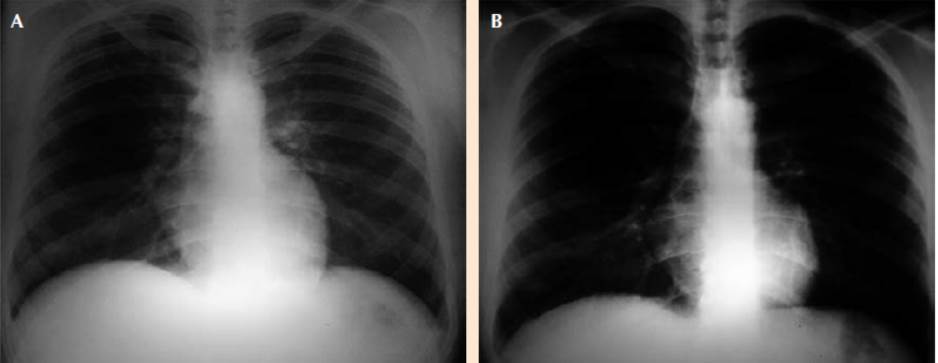

Paciente masculino de 24 años de edad, procedente de área urbana, sin antecedentes patológicos, acudió al servicio de consulta externa de Cirugía del Hospital Regional Santa Teresa, Comayagua, Honduras, con antecedente de dolor abdominal de dos meses de evolución, localizado en el hipocondrio derecho, irradiado a la región escapular ipsilateral, tipo cólico, de intensidad moderada-severa, exacerbado con alimentos grasos, atenuado con analgésicos. Se realizó ultrasonido abdominal que reportó dos litos móviles a la lateralización, con tamaño de 10 x 15 mm en la vesícula, por lo que se ingresó para procedimiento quirúrgico electivo (colecistectomía). Se realizó cirugía dos días después de su ingreso. En el posoperatorio inmediato, quince minutos posextubación, el paciente inició con cuadro clínico de disnea súbita acompañado de hemoptisis, cianosis y alteración del estado de conciencia. Al examen físico se observó Glasgow 13/15, paciente taquipneico (FR = 40 rpm) con evidente dificultad respiratoria, saturación de oxígeno 79%, sin signos de inestabilidad hemodinámica. Mucosa oral húmeda, con restos hemoptoicos; corazón: taquicárdico, sin soplos; a la auscultación pulmonar: abundantes roncus y crepitantes bilaterales, sin áreas de hipoventilación. Los exámenes de laboratorio reportaron leucocitosis, trombocitopenia y acidosis metabólica (Cuadro 1). A su vez, se realizó radiografía posteroanterior de tórax que evidenció infiltrado intersticial bilateral algodonoso, en “alas de mariposa”, característico de edema agudo de pulmón (Figura 1). El tratamiento consistió en apoyo ventilatorio con oxígeno en mascarilla de reservorio a 10 L por minuto, administración de esteroides (metilprednisolona) y diuréticos (furosemida) durante 48 horas con alivio completo del cuadro a las 72 horas del posoperatorio (Figura 2).

Figura 2 A. Radiografía posteroanterior de tórax, paciente con tratamiento inicial de 24 horas, se observa alivio parcial del parénquima pulmonar, con disminución de edema agudo de pulmón. B. Radiografía posteroanterior de tórax 72 horas posterior al tratamiento. Se observa alivio completo del cuadro.

El tratamiento del edema agudo pulmonar por presión negativa varía desde oxigenoterapia no invasiva, restricción de fluidos endovenosos, hasta ventilación mecánica invasiva con presión positiva.14 El tratamiento médico es todavía controvertido, se prescriben con frecuencia diuréticos en dosis moderadas y corticoesteroides sistémicos.15 En la mayoría de los casos el edema agudo pulmonar por presión negativa se alivia en 12 a 24 horas con diagnóstico y tratamiento tempranos.16 Sin embargo, cuando se retrasa el diagnóstico, los pacientes tienen tasas de mortalidad que van desde 11 hasta 40%.6 La evolución del paciente fue favorable, con mejoría en las primeras 24 horas de iniciado el tratamiento y se alivió a las 72 horas posteriores a la cirugía.